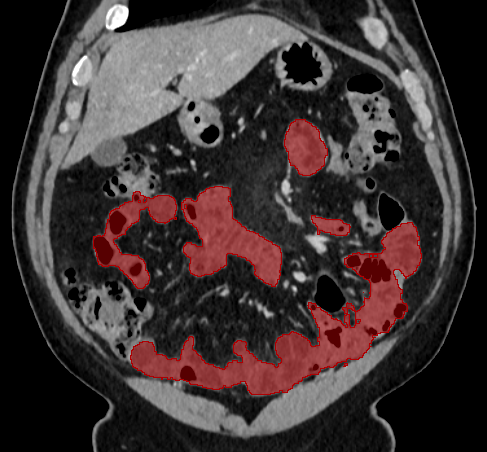

Over the years, there have been attempts to develop automatic methods for small bowel segmentation, especially using deep learning. The small bowel was included in segmenting multiple organs-at-risk for radiotherapy treatment planning of affected tissues, such as pancreatic and cervical cancers, in CT scans [8, 9, 13]. Although the results obtained for the small bowel are reasonable, some of their data included only the part of the small bowel that is closest to the target area, which needed to be dose-evaluated [8, 9]. In [13], the rough bowel location was detected instead of performing pixel-accurate small bowel segmentation. There have been only a few previous works dedicated solely to automatic small bowel segmentation [12, 14, 21]. While the specific anatomic relationship between the mesenteric vasculature and the small bowel is used to guide the small bowel segmentation in [21], a cylindrical shape constraint is applied during training of the small bowel segmenter in [14]. Although each of the works showed reasonable performance for particular datasets, their generalizability across different datasets was not evaluated. A CT scan is acquired using a specific imaging protocol depending on the purpose of the investigation, which includes the use of different contrast media and scan timing. Thus, the appearance of the small bowel may be different across datasets as exemplified in Figure 1. It is observed in our experiment that, when trained on one dataset, the model does not generalize well to another dataset due to the domain shift (section 3).

In this paper, we present a novel unsupervised domain adaptation method for small bowel segmentation, which is based on feature disentanglement. Although the absolute intensity values in CT scans (Hounsfield units) carry important information on specific substances of the human body, thus could provide a clue of being specific tissues and organs, they may be variable according to the imaging protocol. Figure 1 shows example CT scans that were acquired with and without oral contrast administration. The absolute intensity values are no longer a strong clue for the small bowel when we train and test across the datasets. Non-intensity features like texture and shape may be more useful. For example, local textures of the valvulae conniventes, which are circular folds on the inner surface of the small bowel, are more recurrent across the datasets.

A

B

B

C

C

D

D